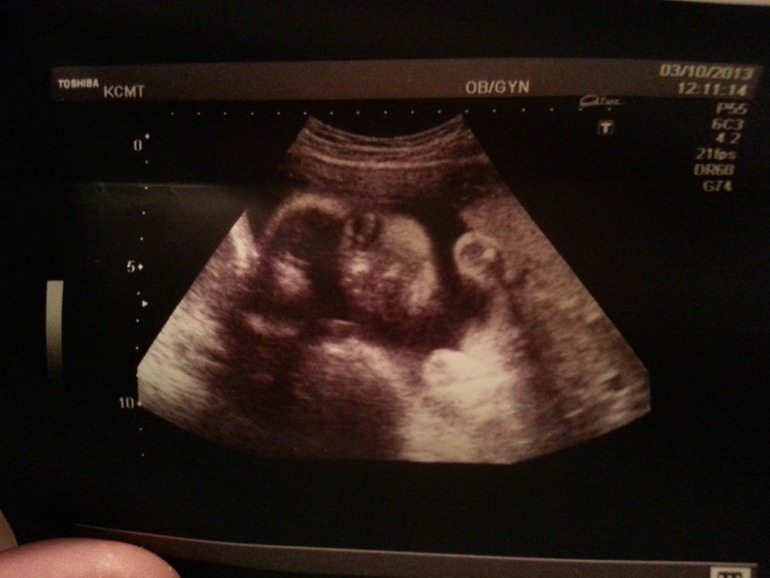

Неделю назад были с мужем и сыном на УЗИ. У нас все хорошо. Претензий нет. Лежит головкой вниз. Весил 1164 г. Муж видел, как Мася зевает ) Вот он наш сладкий ))

Вдм чуть больше чем положено.